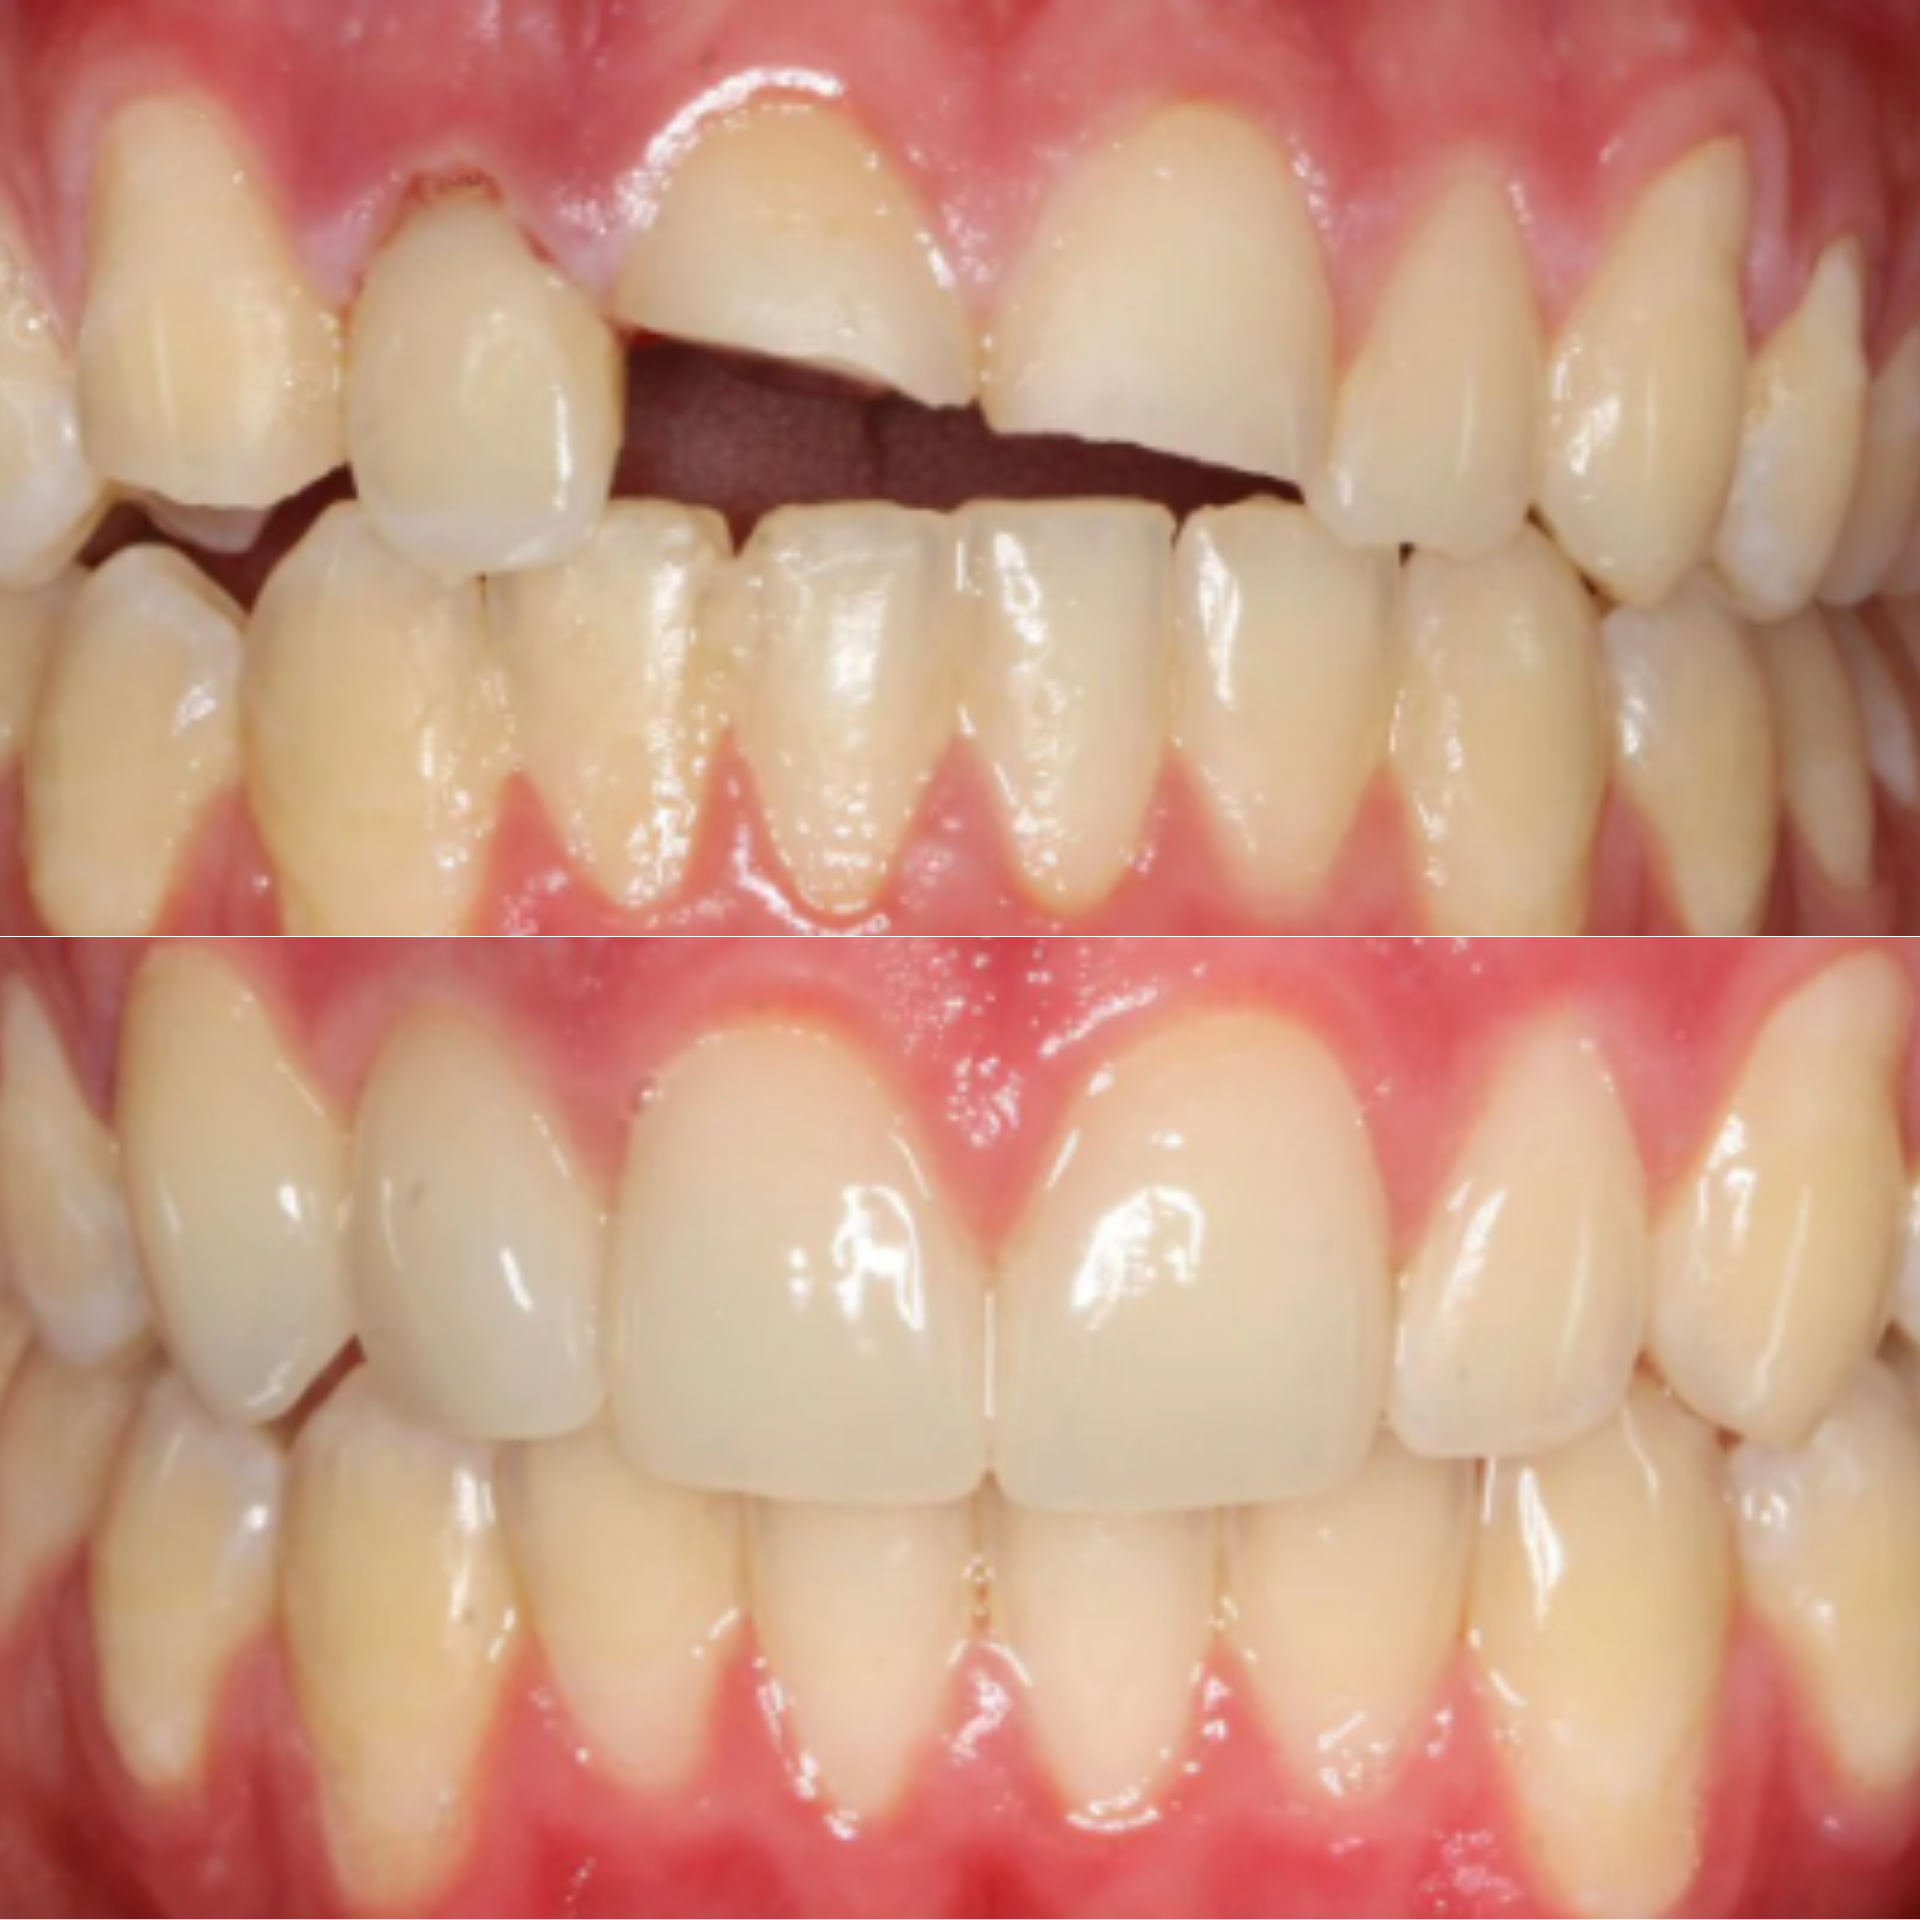

At Elite Dental Group, we provided emergency care that included root canal treatment on the upper central incisors. Dr. Satish Palayam performed an immediate implant placement for the right lateral incisor and completed a crown lengthening procedure on the palatal side of the right central incisor to support proper restoration. A provisional bridge was then placed to maintain both function and esthetics throughout the healing phase.

After a four month healing period, the final crowns were placed on the central incisors, and the implant for the right lateral incisor was successfully restored and finalized.